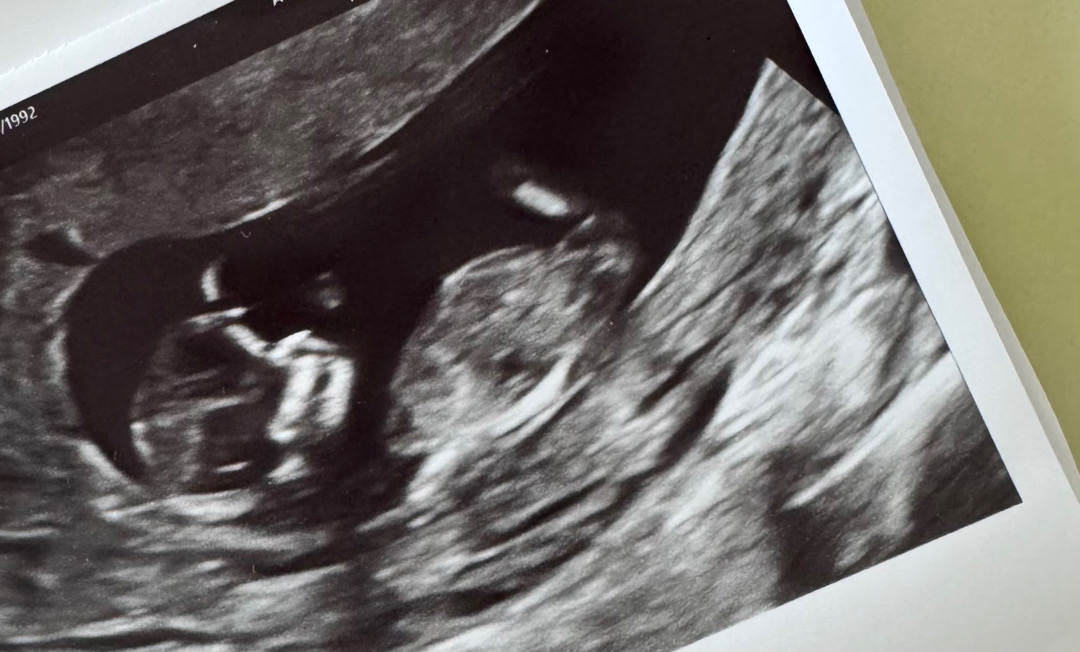

11주5일차 성별예측 가능할까용 🙏🤍

처음으로 글 올립니다~ 사진으로 성별 예측 가능할까요?!?! 미리 감사합니다~! 😊😊

왠지 딸 같네요~